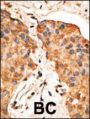

Applikationen WB, FC, IHC-P

IHC-P: 1:50~100